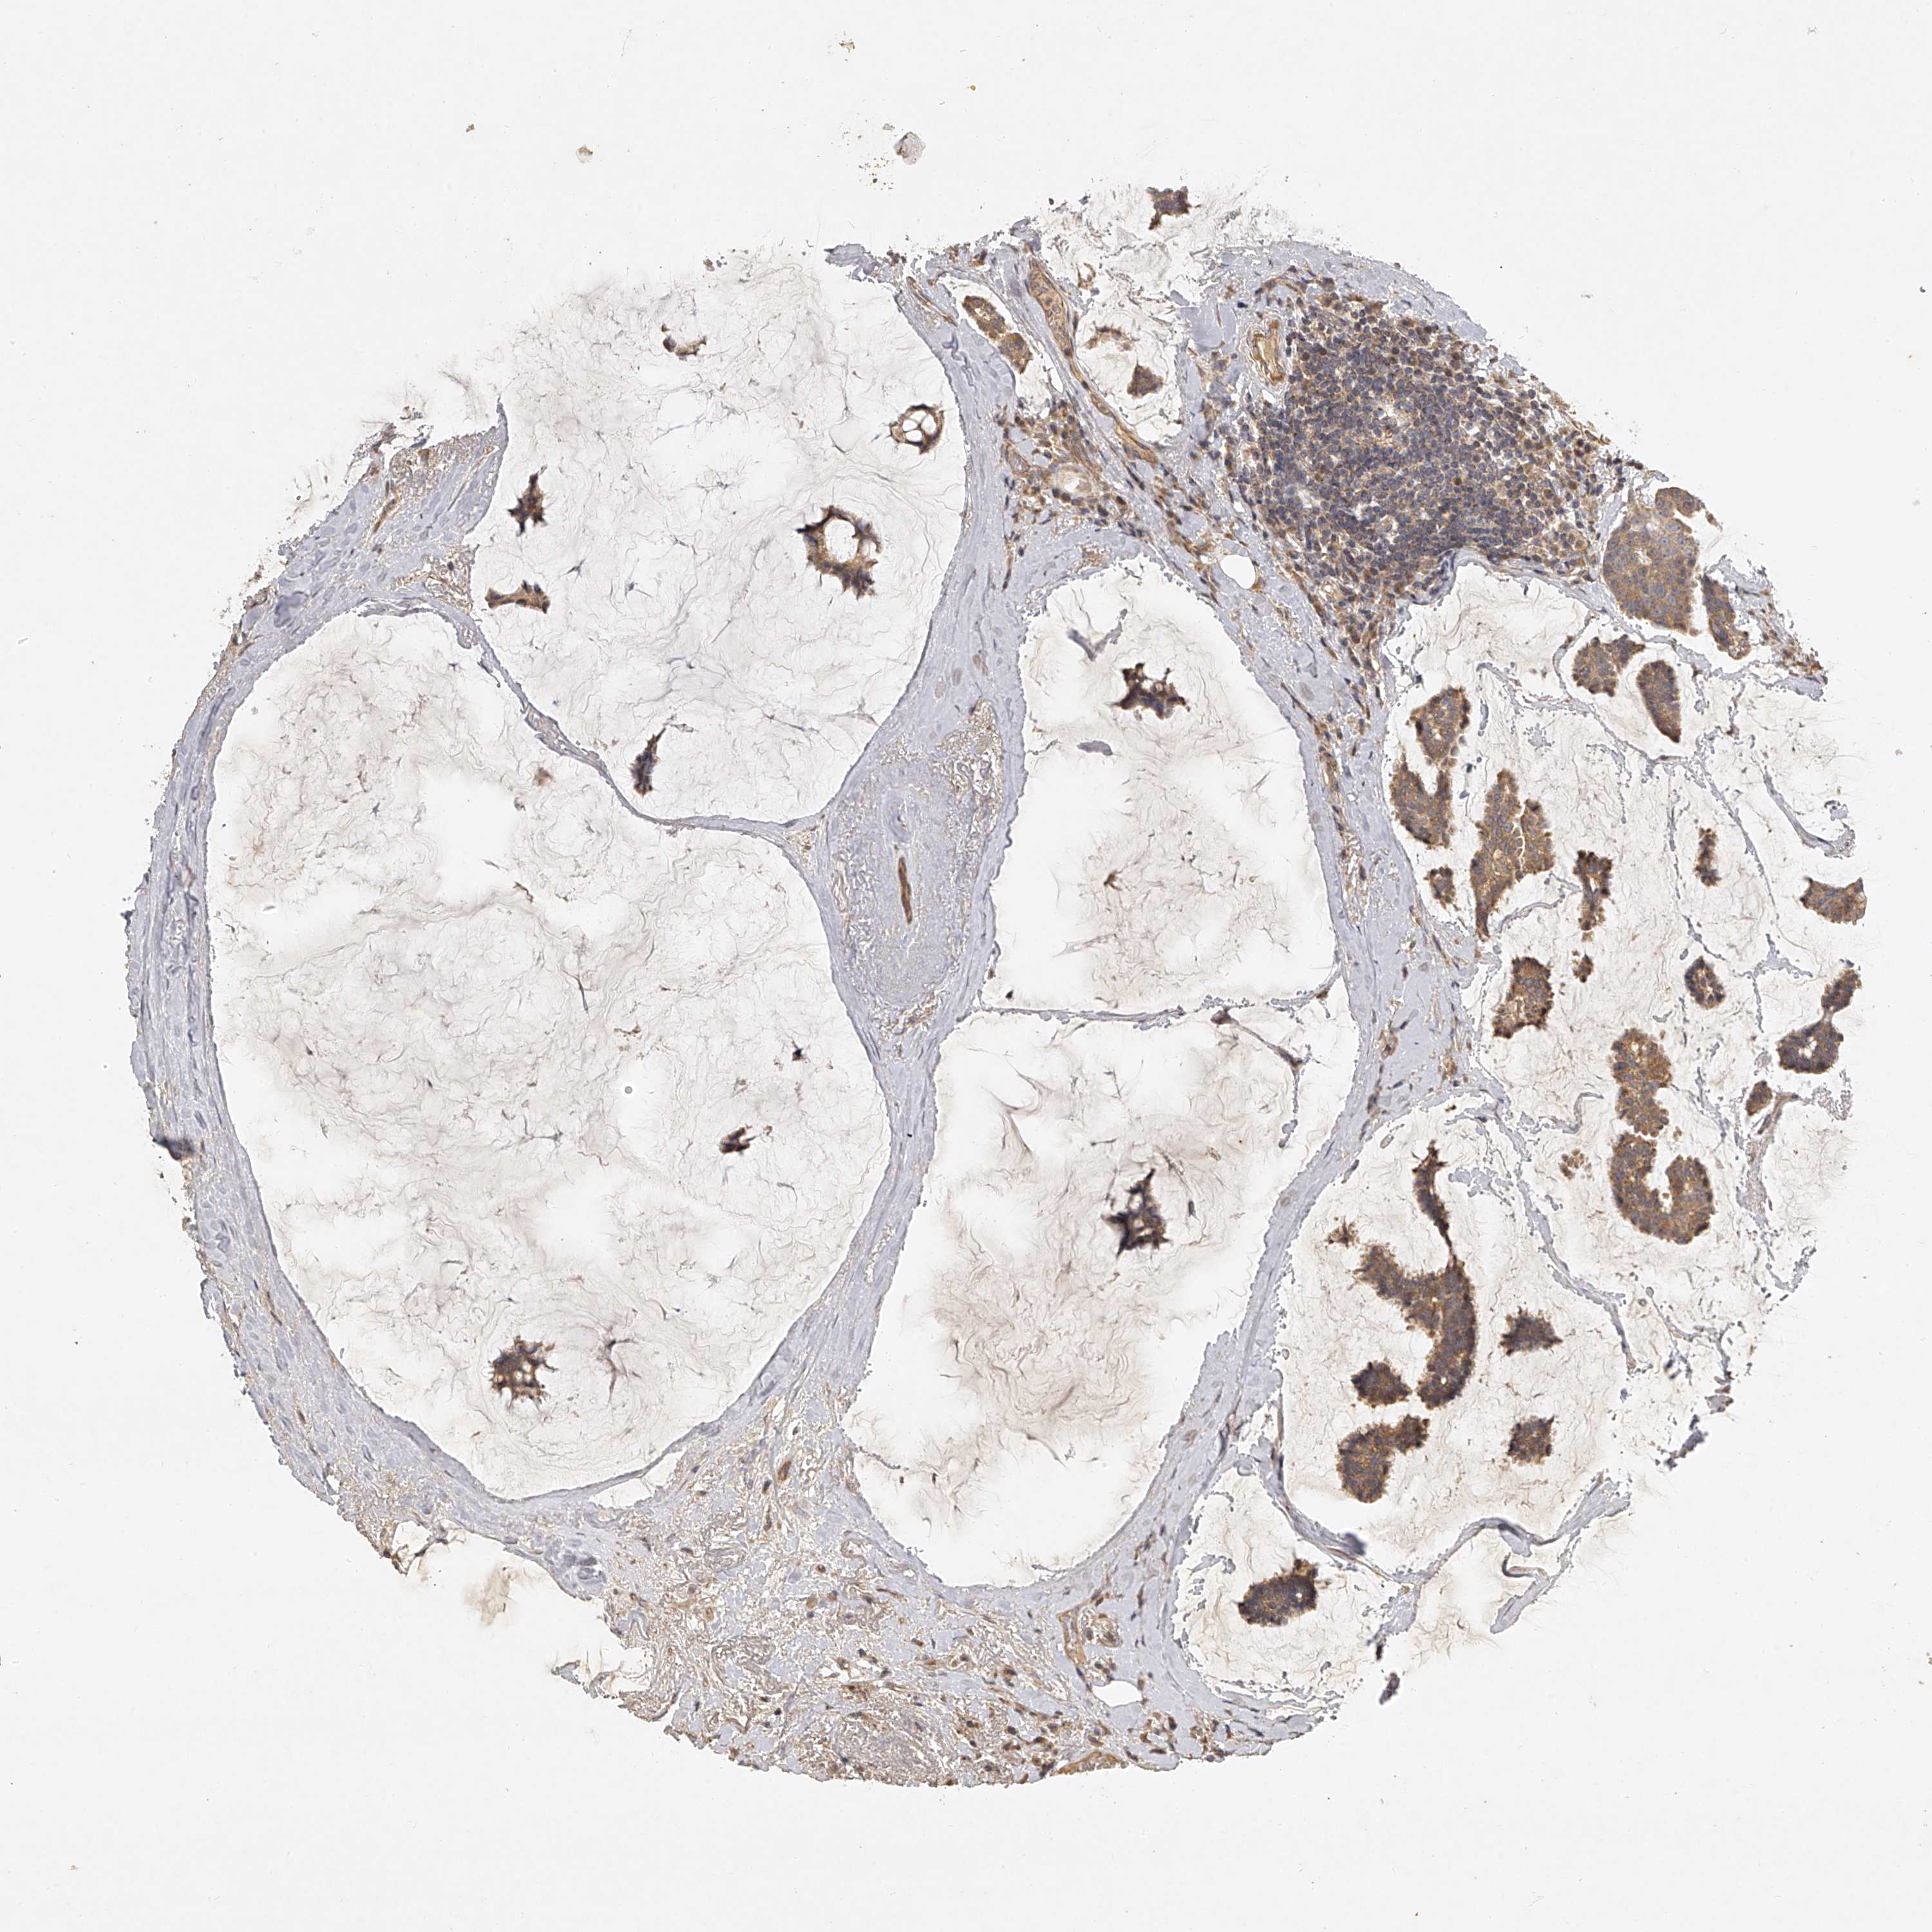

CANCER BREAST CANCER Show tissue menu

BRCA TCGA BRCA VALIDATION PROTEIN EXPRESSION

Breast cancer

Human cancer